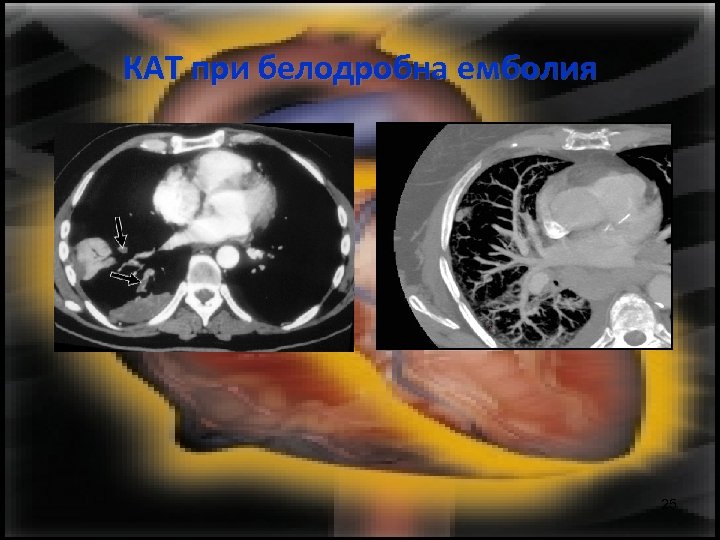

КАТ при белодробна емболия 25